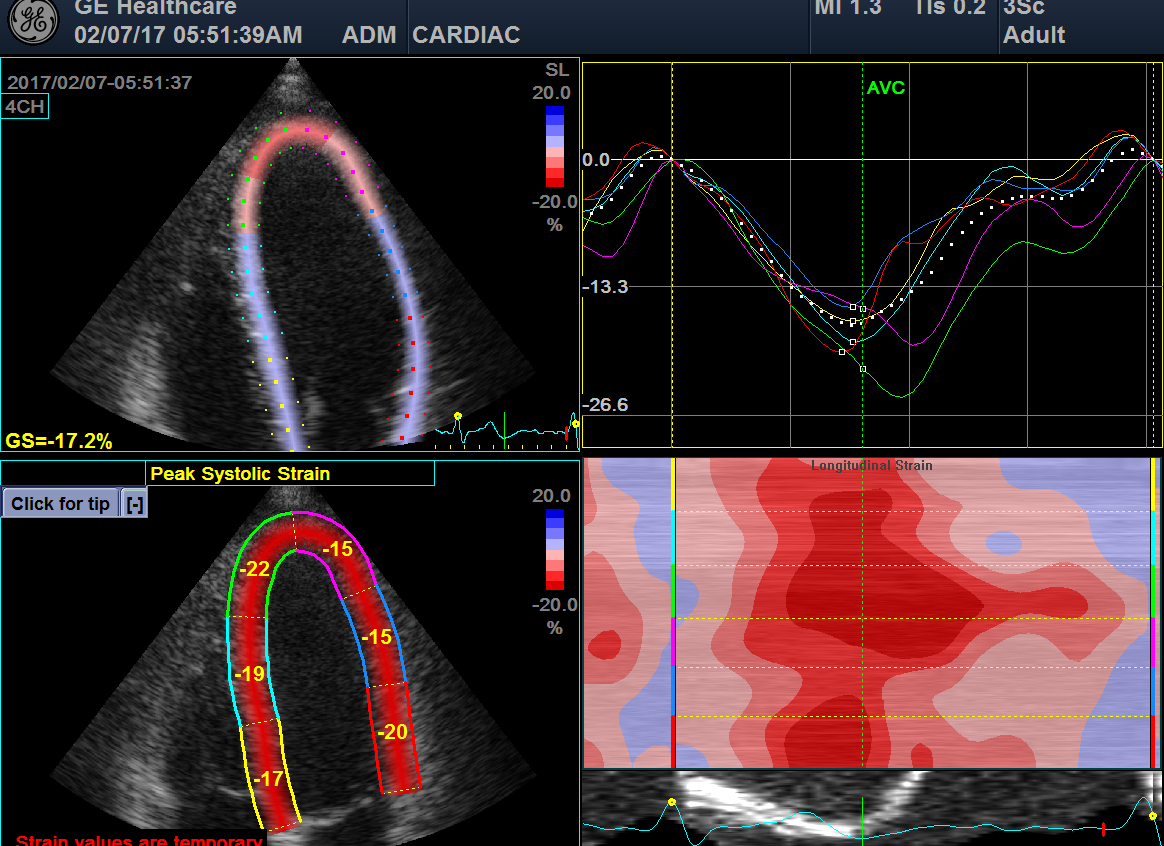

심장 초음파는 초음파를 이용하여 실시간으로 심장의 움직이는 모습을 관찰할 수 있으며, 심장의 해부학적 구조의 이상, 심장 기능, 심장 내 압력 등을 실시간으로, 비침습적으로 관찰할 수 있는 검사법입니다.

대부분의 심장 질환에 매우 중요하게 사용되고 있으며, 많은 심장 질환에서 높은 정확도를 가집니다.